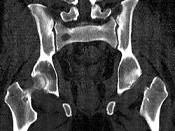

问题 男,46岁,双髋部疼痛,实验室检查血钙升高,尿本周蛋白(+),结合图像,最可能的诊断是?(?)

选项 A.骨髓瘤 B.骨质疏松症 C.骨转移瘤 D.骨囊肿 E.动脉瘤样骨囊肿

答案 A